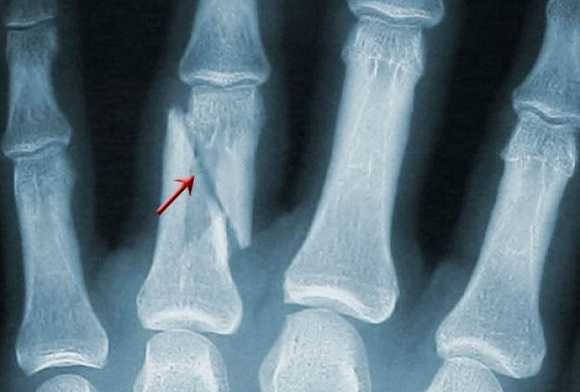

Наиболее распространённым диагнозом является перелом пальца или перелом кисти руки - более 30% всех переломов. Причем зачастую такая проблема случается у детей, на организм которых лучевая нагрузка крайне нежелательна. Поэтому родители сомневаются, нужно ли проводить процедуру рентгенографии, если существует достаточно клинических признаков перелома: отечность, синюшность тканей, деформация естественной формы, значительные болевые ощущения, усиливающиеся во время движения, ухудшение подвижности пальцев. По мнению специалистов, рентгенограмма все равно необходима для того, чтобы визуализировать взаимное расположение отломков костей и суставов, состояние близлежащих тканей. Тем более, что у переломов пальцев симптомы очень схожи с признаками вывиха или ушиба. Поэтому, чтобы не рисковать, а назначить адекватную и своевременную терапию, необходим рентген. Доза при таком виде рентгенодиагностики составит всего 0,001 мЗв, что соответствует дозе природного облучения, полученного менее чем в течение одного дня.

В структуре кисти - довольно много мелкоразмерных костей. Потому и видов переломов кисти существует тоже много:

- открытый и закрытый;

- абсолютный разлом или трещина;

- множественный или изолированный;

- диафизарный (линия перелома располагается на теле кости), околосуставной (линия перелома - между концом кости и ее телом) и внесуставной (линия надлома - на конце кости);

- первичный (появляется при первичном травмировании в момент воздействия силы) и вторичный (смещение случается позже, в результате воздействия прикрепленных к сломанным костям мышц);

- стабильный (отломки остаются на прежнем месте) и нестабильный (случается вторичное смещение отломков).